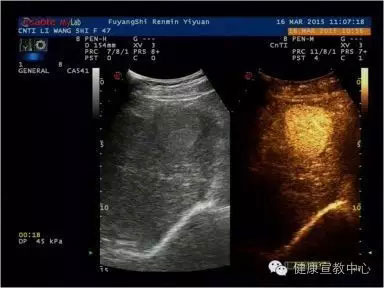

(超聲造影輔助分類)

(肝臟超聲造影)